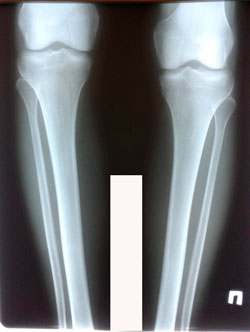

Дата операции - 26.08.2020

Дата снятия аппаратов - 27.11.2020

Срок сращения - 90 дней.

image-26-08-20-06-25-4.jpg

image-26-08-20-06-25-2.jpg

image-27-11-20-07-26-1.jpg